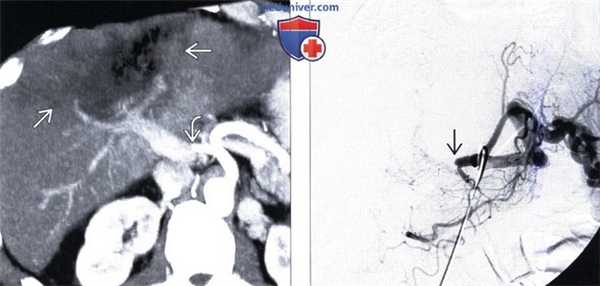

(Слева) На аксиальной КТ с контрастным усилением определяется вертикально ориентированный гиподенсный участок, распространяющийся от краниальных до каудальных отделов печени, отграниченный прямой демаркационной линией, обусловленный лучевой терапией по поводу лимфомы.

(Справа) На аксиальной КТ с контрастным усилением визуализируется ровная демаркационная линия, отделяющая поврежденный участок в левой доле печени, обусловленный лучевой терапией по поводу рака пищевода. Обратите внимание, что левая печеночная вена, проходящая в поврежденном участке печени, не выглядит патологически измененной. (Слева) На аксиальной КТ определяется снижение плотности задних сегментов печени, отделенных от не измененной паренхимы четкой демаркационной линией. Гиподенсные участки паренхимы соотносятся с зоной, подвергнутой эмболизации с использованием микросфер иттрия-90, по поводу гепатоцеллюлярного рака. Обратите внимание, что задняя ветвь правой долевой ветви воротной вены, проходящая внутри измененного участка паренхимы печени, выглядит обычно.

(Справа) На КТ с контрастным усилением у этого же пациента визуализируются жизнеспособные сателлитные очаги ГЦР в передних сегментах печени, которые не подвергались облучению.